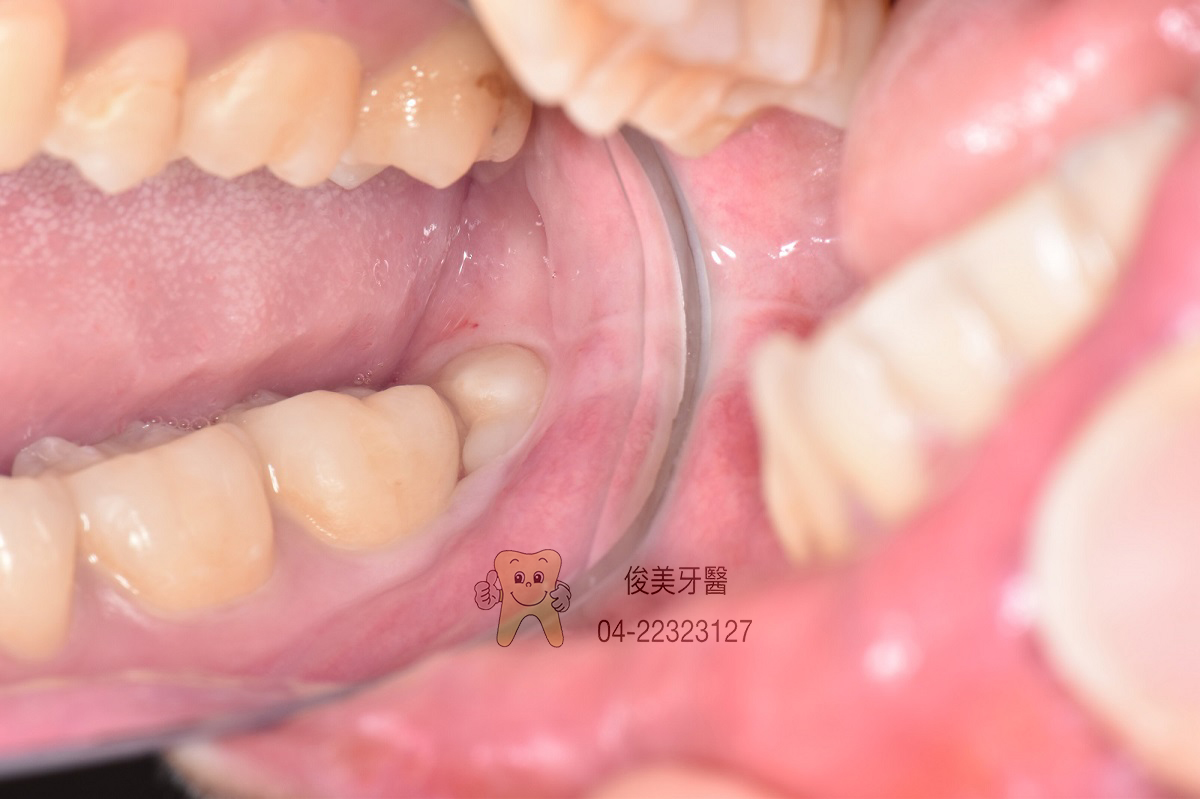

患者的智齒為水平生長,只露出一角,但塞東西後很難清潔,所以決定拔除。

因牙齒埋在骨頭裡,拔除後就會有一個窩洞,需強力冰敷三天,幫助止血、消腫和穩定血塊,並注意傷口清潔。

縫合幫助傷口癒合,也防止食物直接塞入傷口中。